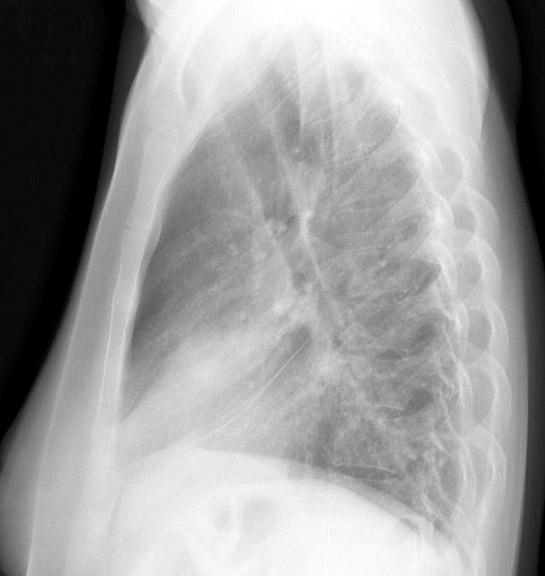

Gallery Lobar Collapse RML Collapse Case 1 Lateral

Case 1 Lateral